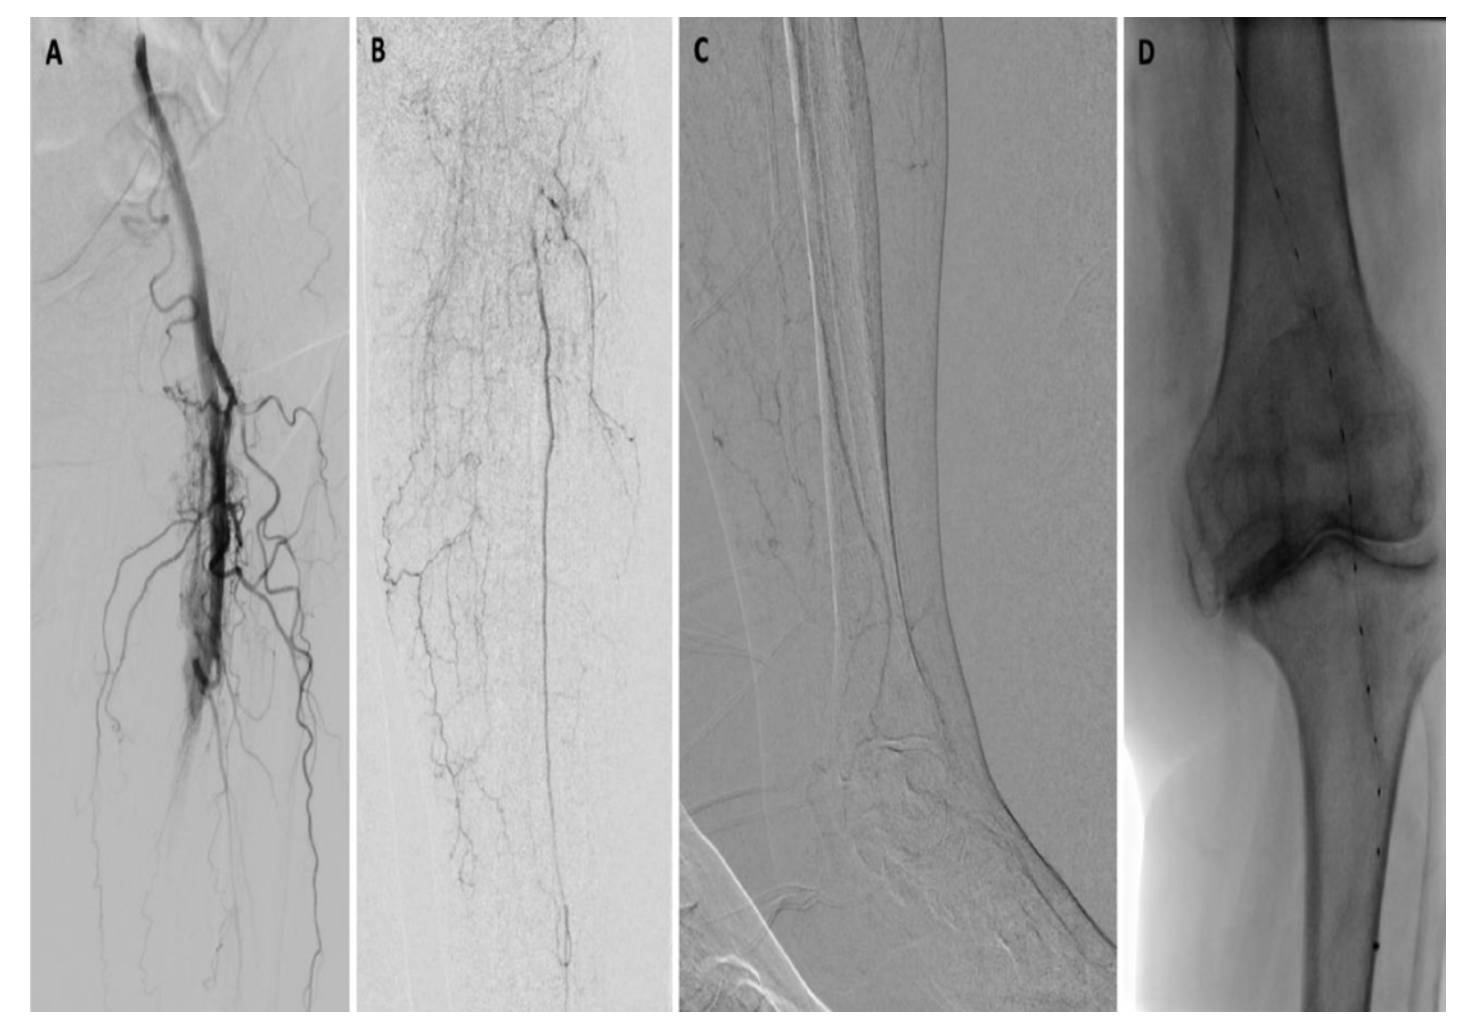

Diagnostic angiography (Figure 3) revealed a long-segment occlusion of the femoropoliteal artery beginning approximately 10 cm from the origin of the superficial femoral artery, at the level of the arteriovenous fistula. Numerous collaterals from the profunda artery were seen through the thigh and knee. There was faint reconstitution of the proximal peroneal artery. No significant below-ankle pedal reconstitution was noted.

The repeat angiogram demonstrated restoration of flow throughout the femoropopliteal segment, with direct inline flow to the peroneal artery (Figure 4). On this study, distal peroneal artery collaterals and perforators were seen reconstituting pedal arteries, not demonstrated previously, in keeping with the patient’s markedly improved physical exam. There was near resolution of the previously identified superficial femoral arteriovenous fistula. Despite the slightly ectatic appearance of the distal popliteal artery and tibioperoneal trunk, no true aneurysmal dilation was identified on the recent CTA. An approximate 80% stenosis was present within the tibioperoneal trunk, at the same location where difficulty was encountered in advancing the wire on the previous day. Angioplasty of this segment was performed with a 3.0 x 60 mm balloon in order to improve single-vessel inline flow to the foot.

Following angioplasty, the repeat angiogram demonstrated resolution of the tibioperoneal stenosis, but with a new, nearly occlusive 5 mm filling defect in the proximal peroneal artery (Figure 5). Several therapeutic options were discussed and a decision to perform spot laser thrombolysis was made. Using a 0.9 mm Turbo-Elite laser atherectomy catheter (Philips), a total of two passes were performed across the proximal peroneal artery at low and moderate fluence and rate settings. The repeat angiogram demonstrated unsuccessful lysis, with the embolus now having migrated into the mid segment of the peroneal artery, resulting in complete occlusion. Fortunately, an .014-inch wire remained across the occlusion and a decision to perform long-segment angioplasty in order to macerate the lesion was made. The angioplasty was performed with slow and prolonged inflation of a 2.0 x 220 mm balloon, with the balloon tip in the distal peroneal artery. It also resulted in more distal migration of an occlusive filling defect, bringing complete occlusion of important, unnamed collaterals to the pedal arteries, as well as the perforating branch of the peroneal artery.